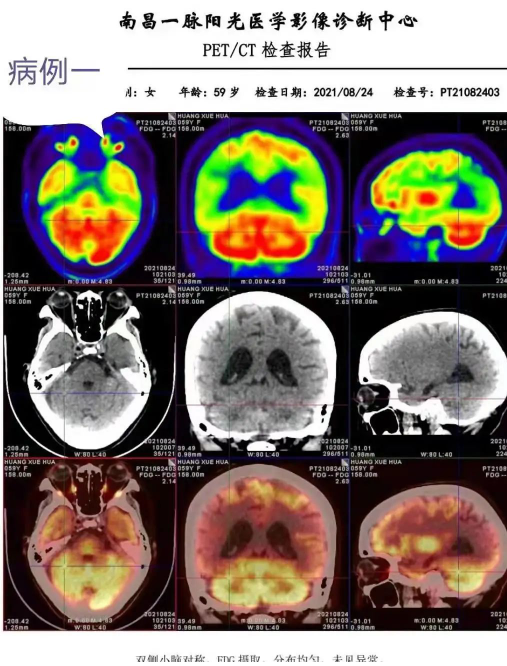

8月27日,新余影像中心组成AD科研工作小组(新余影像中心+神经内科+南昌影像中心),采用认知功能量化评分表,开展应用影像多功能成像技术(磁共振多功能成像和脑部PET —CT),并与结构影像AI分析结合,对阿尔兹海默病(AD)的诊断与鉴别。